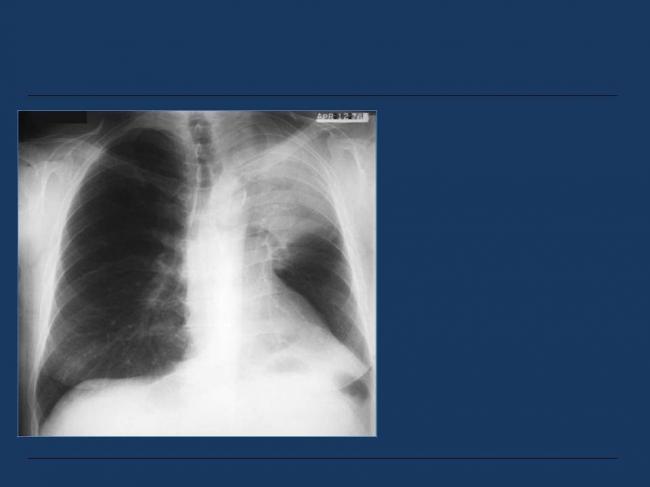

Помимо опроса и объективного осмотра, включающего перкуссию и аускультацию грудной клетки, проводят рентгенологическое исследование в двух положениях тела (в 2-х проекциях). Это основной метод обнаружения ателектазов легких.

На рентгеновских снимках выявляют следующие признаки, указывающие на спадение легочной ткани:

Однородное затемнение в области поражения. Размеры тени зависят от вида ателектаза: при долевом выявляется обширное затемнение, при сегментарном — в виде клина или треугольника, расположенного вершиной к корню легкого, дольковые ателектазы множественные и похожи на очаговую пневмонию. Дистензионный ателектаз расположен низко, около диафрагмы, имеет небольшие размеры и вид поперечных полос или темных дисков. Смещение органов: при компрессионном ателектазе смещение наблюдается в здоровую сторону, так как на стороне поражения давление больше, при обтурационном, наоборот – смещение будет в сторону ателектаза, так как на стороне поражения нарастает притягивающее отрицательное давление. Подъем купола диафрагмы – это видно по расположению печени.

Помимо всего перечисленного выше, рентгеноскопия, то есть исследование «вживую», позволяет увидеть куда смещаются органы в зависимости от фазы дыхания, кашля. Это является дополнительным признаком ателектаза, помогающим выявить тип болезни.

Во время инструментальных диагностических манипуляций важно не только установить наличие ателектаза и его точную локализацию, но и уточнить объем спавшейся ткани, чтобы определить правильную тактику лечения и объем лечебных манипуляций. На рентгенограмме для диагностики ателектаза имеет значение состояние не только ткани легких, но и корней легких, ребер, органов средостения, купола диафрагмы, плевры, плевральной полости и даже позвоночника (будет наблюдаться его сколиотическое отклонение в направлении выпуклости в сторону пораженного легкого)

На рентгенограмме для диагностики ателектаза имеет значение состояние не только ткани легких, но и корней легких, ребер, органов средостения, купола диафрагмы, плевры, плевральной полости и даже позвоночника (будет наблюдаться его сколиотическое отклонение в направлении выпуклости в сторону пораженного легкого).